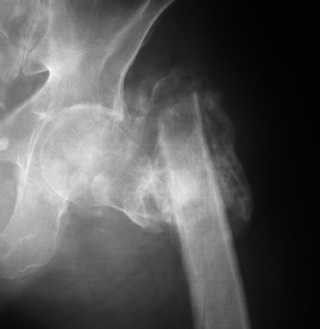

Последствия чрезвертельного перелома бедренной кости

Пациент С., 45 лет, преподаватель одного из ВУЗов г. Москвы, 3 года назад получил чрезвертельный перелом левой бедренной кости, по-поводу чего в одной московских больниц лечился методом скелетного вытяжения.

Развилось нагноение в области перелома, после чего имелся свищ по наружной поверхности бедра (рис. 1 - фистулография). Через 1 год воспалительный процесс был купирован. Свищ закрылся самостоятельно.

При осмотре: левое бедро укорочено на 10 см, нижняя конечность находится в положении наружной ротации 50 градусов, свищей нет.

Рентгенологическая картина — рис. 2. При КТ: признаков аваскулярного некроза головки бедренной кости нет, головка находится в ретроверсии (рис. 3).

1 месяц назад нами произведена остеотомия костной мозоли, наложен спице-стержневой аппарат на левые бедро и таз. На 14 сутки после операции при дистракции в аппарате отмечено нагноение послеоперационной раны. Края раны были разведены, выполнена контраппертура для ее дренирования. На данный момент воспаление купировано (рис. 4,5). В настоящий момент длина конечности восстановлена, ротация кнаружи устранена (рис. 6). На сем 1 этап лечения мы считаем законченным.

А вот по-поводу 2 этапа мы пока не пришли к единому мнению. В нашем отделении есть горячие сторонники остеосинтеза бедренной кости и не менее горячие приверженцы выполнения эндопротезирования тазобедренного сустава. С каждым днем страсти накаляются все больше.

1 вариант — «Остеосинтез». Фиксация штифтом Гамма с антибактериальным покрытием (правда, шеечный винт цементом с антибиотиком покрыть не получится). Вопрос: как вывести головку бедренной кости в положение антеверсии, что бы шеечный винт при фиксации прошел через шейку и головку бедренной кости?

2 вариант — «Эндопротезирование». Иссечение костных разрастаний, удаление головки бедренной кости, установка спейсера с антибиотиком, эндопротезирование через 6-10 месяцев.

Вопрос: вариант очень травматичный, что обусловливает высокий риск осложнений; и еще, удержится ли спейсер в вертлужной впадине после операции?